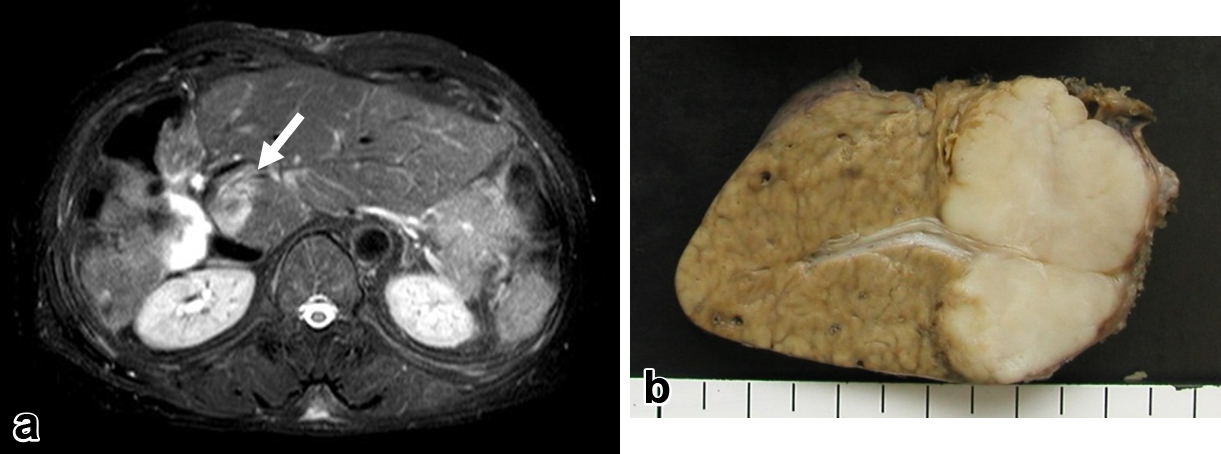

臨床経過(3):初回術後2年9か月(2回目手術後8か月),EOB造影MRIで残肝S1に3 cm大の腫瘤を認めた(Fig. 3a).2回目手術時と同様に肝外病変はなく,単発のICC肝内再々発と判断し,全身状態良好であったことから肝S1部分切除術を施行した(Fig. 3b).術後に改めて化学療法の導入を検討し,患者が同意されたためS-1内服(80 mg/日,2週間内服,1週間休薬)を開始したが,好中球減少を来し,全身倦怠感が持続遷延するため開始後6か月で終了した.

a) 2 years and 9 months after the initial operation, follow-up abdominal contrast MRI revealed a mass of 3 cm in segment 1 of the remnant liver (arrow). b) Macroscopic view of the resected specimen in the third operation showing a white solid tumor of 3 cm in size.